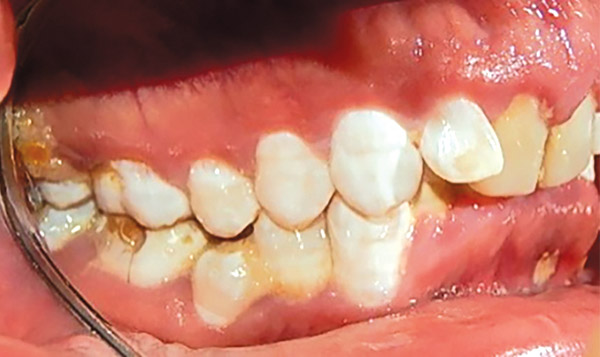

En las fotografías intraorales se muestra la fluorosis dental Tf4 y Tf7, las relaciones molares clase II molar y canina bilateral (Figura 3 y 4), el apiñamiento severo superior e inferior, con el órgano dental 35 en infraoclusión. El overbite aumentado y las líneas medias dentales no son coincidentes (Figura 5), las formas de arco superior e inferior son cuadradas (Figura 6 y 7).

Figura 3. Intraoral derecha.